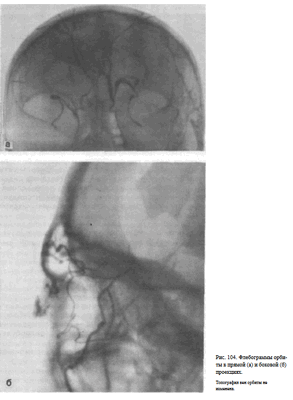

УКЛАДКИ ФЛЕБОГРАФИЯ ОРБИТЫ

Назначение исследования — определение объемного процесса в полости глазницы на основании изменения топографии венозной сети, главным образом верхней глазничной вены.

Поперечную вену носа и лицевую вену сдавливают с помощью ватных подушечек. После введения 1—2 мл 0,5 % раствора новокаина максимально быстро—за 1—1,5 с—вливают 3—4 мл 50% раствора гипака и производят серию рентгенограмм в задней обзорной и боковой проекциях. Для этого используют специальный ангиографический комплекс, включающий две рентгеновские трубки и две приставки для быстрой смены кассет. При отсутствии такого комплекса после введения контрастного вещества поочередно выполняют прямой и боковой снимки.

Информативность исследования. Топография верхней глазничной вены постоянна. В норме на флебограмме орбиты в боковой проекции верхняя глазничная вена выявляется под верхней ее стенкой. Она имеет плавные изгибы. Часто видны коллатеральные вены, соединяющие ее с нижней глазничной веной, менее постоянной в своей топографии. На флебограмме

орбиты в прямой задней проекции верхняя глазничная вена отображается в форме ромба (рис. 104, а, 6). Отклонение в пробеге верхней глазничной вены, оттеснение ее, а также обрыв, как правило, связаны с объемным процессом в полости глазницы.